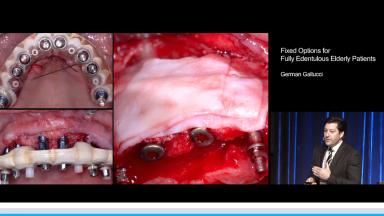

Fixed Options for Fully Edentulous Elderly Patients

In this lecture German Gallucci discusses the special considerations involved in treating elderly edentulous patients with fixed, implant-supported prostheses. He presents evidence that age and gender are not determinants in the choice between a fixed or removable prosthesis. However, elderly patients may have specific concerns that must be addressed when developing treatment plans aimed at replacing their missing teeth. Multiple cases are presented to illustrate this deliberate approach to fixed prosthetic solutions in elderly patients, including the use of mini-implants and computer-guided planning and surgery.